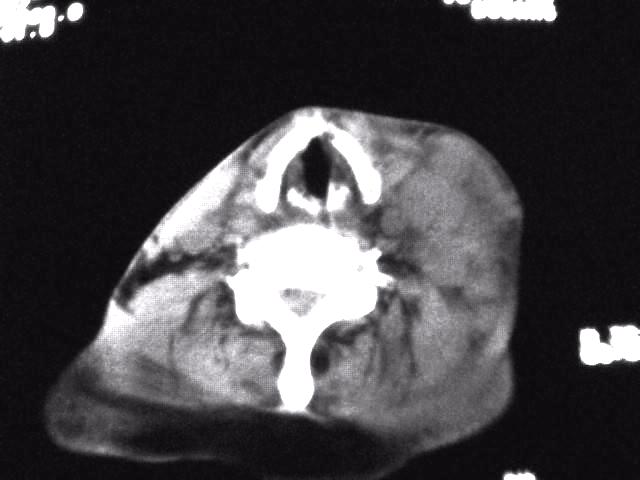

颈部层厚10mm间距10mm连续扫描及增强扫描共24层示:左侧下颈部胸锁乳突肌内侧区域内可见多发软组织结节,密度不均,内可见斑片状低密度区,大小不等,部分融合成块,左侧融合成一块者大约9.0x5.4,与周围肌肉、血管等结构界面不清,骨质未见明显浸润影。左侧锁骨下可见多个软组织结节,与周围界限尚清,左侧锁骨上窝内可见一大软组织肿物,大小约4.7x3.7cm,内密度欠均匀中心可见低密度区。

考虑:左侧颈部及双侧锁骨下多发淋巴结肿。非何杰金氏淋巴瘤可能性大,建议进一步检查。